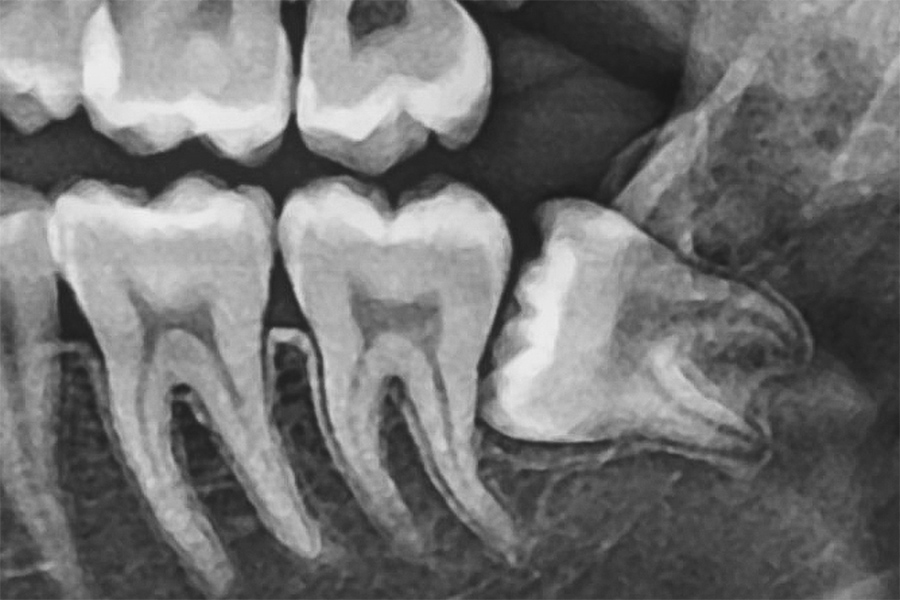

水平埋伏歯の治療について

水平埋伏歯とは、歯茎の中で横向きに生えてしまった歯のことです。これにより、手前の歯を圧迫して痛みや歯並びの乱れを引き起こし、さらに虫歯歯周病の原因にもなります。

このような歯は骨や神経に近い位置にあるため、抜歯には高度な技術が求められます。当院では、精密な診断と高い技術力で、難しいケースの抜歯にも対応しています。他院で治療を断られた場合も、安心してご相談ください。